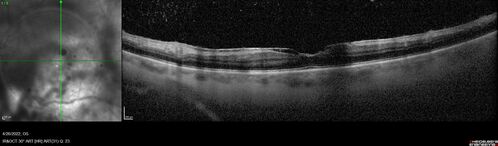

Recurrent toxoplasmosis

63 year old female with history of floaters and vision loss in the left eye.